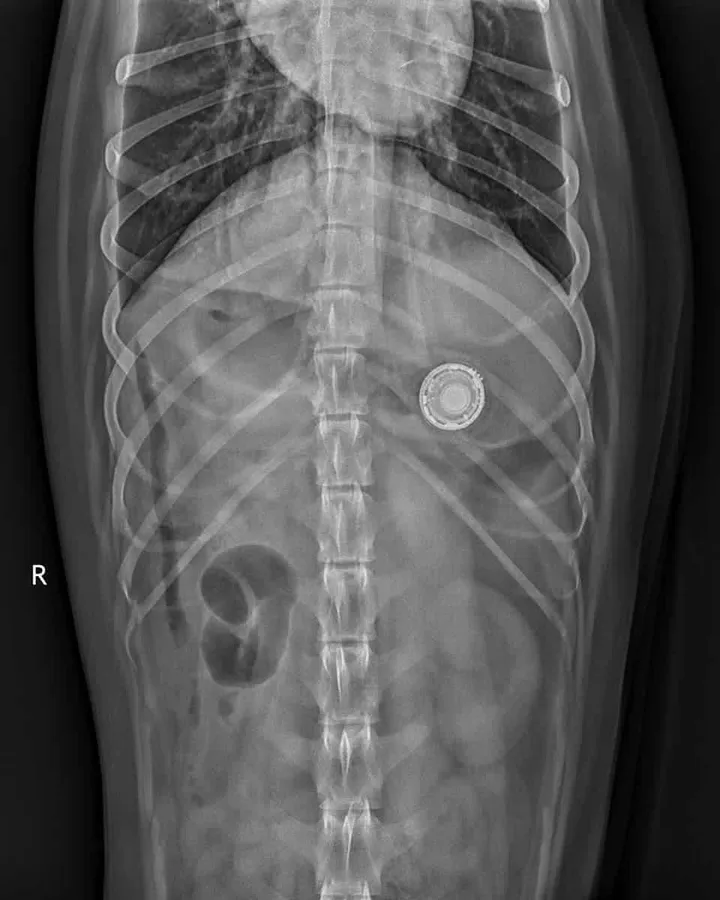

Dog swallows Apple Airtag

According to MacRumors, dog owner Colin Mortimer experienced such an encounter. He found that the AirTag on the dog's collar was missing, so he used the Find My app to track and play the sound. Unexpectedly, the AirTag made a sound from the dog's stomach. Coincidentally, another dog was sent to the emergency room by the owner because of swallowing an AirTag but luckily escaped the danger safely.